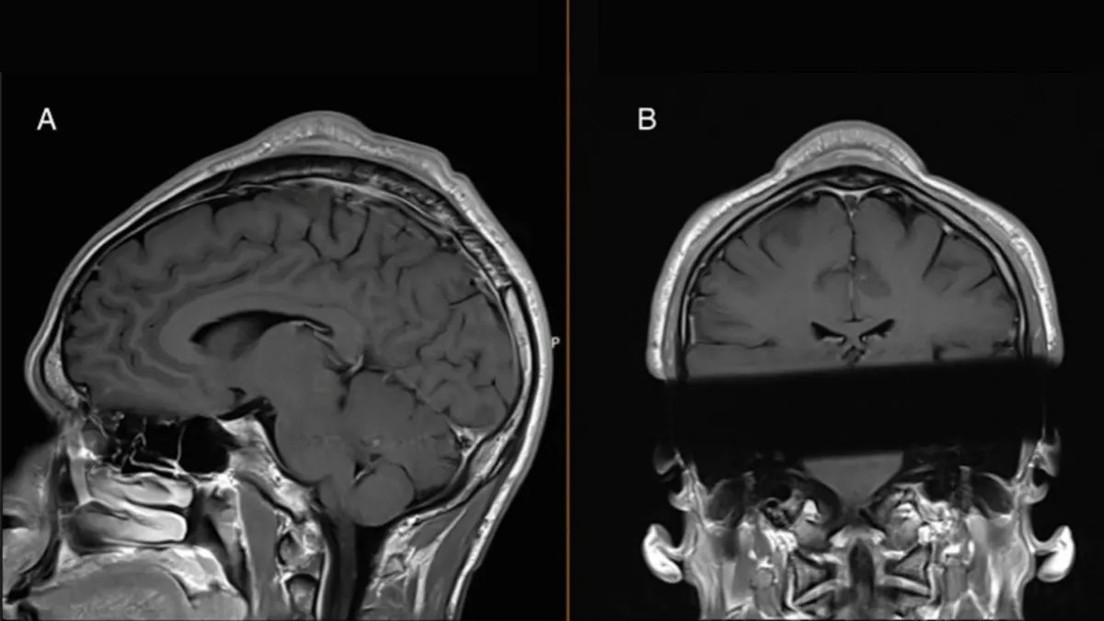

Posteriormente, notó que se le había formado un bulto en el cuero cabelludo, acompañado de pérdida de pelo. En los últimos cinco años, la hinchazón, conocida como 'agujero de giros sobre cabeza' o 'bulto de breaking', creció y se hizo sensible al tacto.

Si bien los médicos extirparon la protuberancia, el tejido cutáneo circundante quedó engrosado. No obstante, el paciente expresó alivio y comentó que ahora puede mostrarse en público sin sombrero ni gorra. "Mucha gente me dice que ya no se nota el bulto y que mi cabeza parece completamente normal", comentó el hombre.